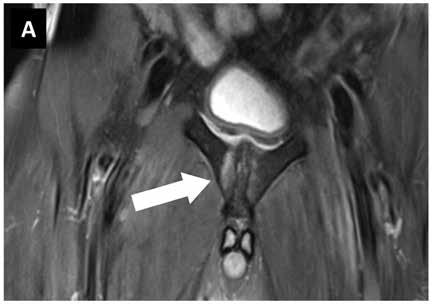

Die Diagnose eines Knochenmarködems erfolgt in der Regel mittels MRT, da es auf Röntgen- oder CT-Scans nicht erkennbar ist. Eine genaue Anamnese und Untersuchung sind ebenfalls wichtig, um die zugrunde liegende Ursache zu identifizieren.

Knochenmarködeme werden typischerweise mit einem MRT identifiziert, da sie auf Röntgen- oder CT-Scans nicht erkennbar sind. Eine genaue Diagnose kann auch durch eine 3D-Analyse mittels spezieller radiologischer Untersuchungstechniken gestellt werden. Invasive Verfahren wie Knochenbiopsien sind heutzutage selten erforderlich.

Ein Knochenmarködem kann durch eine ausführliche Anamnese und eine MRT-Untersuchung diagnostiziert werden. Röntgen- oder CT-Scans können das Ödem nicht erkennen. Bei unklaren Fällen kann auch eine 3D-Analyse mittels spezieller radiologischer Untersuchungstechniken durchgeführt werden. Knochentumore oder Infektionen können ebenfalls zu einem Knochenmarködem führen und sollten bei der Diagnose in Betracht gezogen werden.

Eine ausführliche Anamnese ist die Grundlage für die Diagnose eines Knochenmarködems. Die Diagnose erfolgt in der Regel durch ein MRT, da Röntgen- oder CT-Scans das Ödem nicht erkennen können. Eine genaue Gewebeanalyse kann auch andere Vorgänge wie Entzündungen identifizieren.

Die Diagnose eines Knochenmarködems erfolgt in der Regel mittels MRT, da Röntgen- oder CT-Scans das Ödem nicht erkennen können. Eine genaue Anamnese ist wichtig für die Diagnosestellung und die Einleitung einer geeigneten Behandlung.

Ein Knochenmarködem kann mit verschiedenen Diagnoseverfahren festgestellt werden. Die häufigste Methode ist die Magnetresonanztomographie (MRT), da ein Knochenmarködem auf Röntgen- oder CT-Scans nicht erkennbar ist. Eine MRT liefert auch weitere Informationen über den Zustand des Gewebes und kann dazu beitragen, andere Erkrankungen auszuschließen.